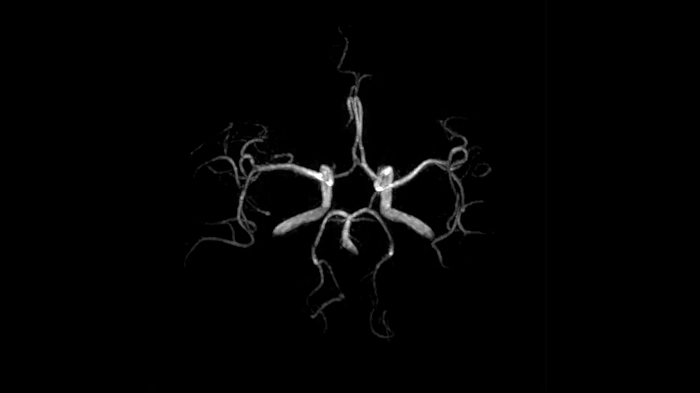

Time-of-flight angiography

To identify vessel occlusions or aneurysms, non-contrast enhanced angiography of the cranial vessels is supportive. High-resolution ToF angiography can also portray small arteries for delicate diagnoses.

0.4 x 0.4 x 0.5 mm2

TA 5:31 minutes

MAC-ID: 7aaaa0195. Image Credit: Siemens Healthineers